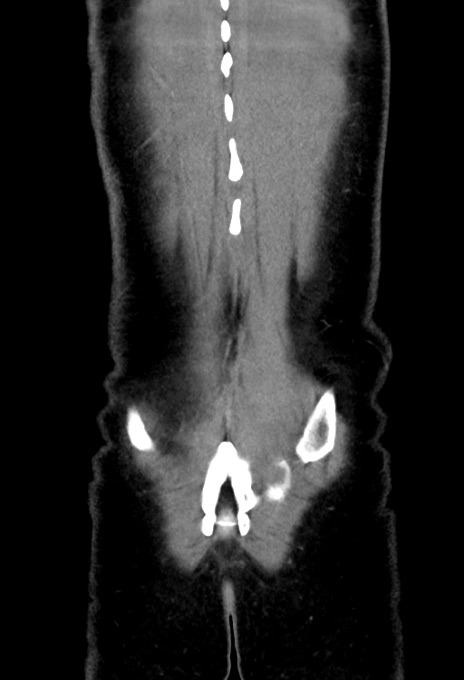

症例17(冠状断像)

【症例】20歳代女性

【主訴】嘔吐、下腹部痛

【現病歴】昨日夕食後に嘔吐し下腹部痛が出現。本日になっても嘔吐持続し改善しないため来院。

【身体所見】意識清明、BT 37.2℃、BP 108/67mmHg、腹部:平坦、やや硬、下腹部正中から右にかけて圧痛あり、反跳痛軽度あり、tapping pain(+)。

【データ】WBC 13600、CRP 14.94